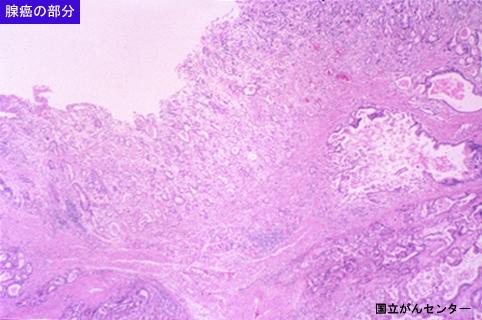

疾患(病理主体)の分類悪性上皮性腫瘍/腺癌

部位(臓器別)食道/下

検査方法ミクロ

腫瘍の肉眼分類3型(潰瘍浸潤型)/

病変の最大径(ミリ)40以上

腫瘍の深達度s(a)